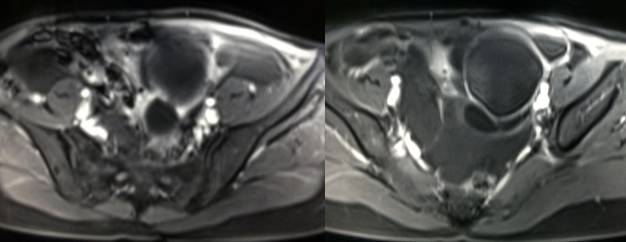

黄体血肿早期:囊内出血较多时,表现为卵巢内近圆形囊肿,囊壁厚,内壁粗糙。

黄体血肿中期:黄体血肿内血液凝固,部分吸收,囊壁变薄而,内壁光滑。

黄体血肿晚期:血液吸收后囊肿变小,转变为白体,内部回声呈实性稍高回

声,与周围卵巢组织分界不清,面靠彩超显示其周围环状血流判断,当血液完全吸收后形成黄体囊肿,囊壁变得光滑,与卵巢其他囊肿难以区分。

根据时间不同MR信号也有所不同,TIWI脂肪抑制序列可以鉴别脂肪和出血。

卵巢囊肿:呈均匀的T1WI 低信号,T2WI 高信号,边界清楚,壁薄,大多数病灶直径≤5 cm,但囊肿的起源及定性诊断困难。

巧克力囊肿:常呈多发的单囊或多囊改变,病灶大小不等,囊壁厚薄不均,囊内信号复杂,囊内或各囊腔间血液因出血时期不同,信号常呈多样性,囊肿内反复出血、破裂,形成相互粘连的多房性囊肿,是其较为特征性的表现。

在鉴别卵巢畸胎瘤、出血性囊肿或巧克力囊肿时,MR 脂肪抑制T1WI 可明确肿块内高信号成分是脂肪还是出血,同时由于脂肪组织与非脂肪组织的共振频率不同,在两者交界处沿磁场频率编码方向出现化学位移伪影,但出血性囊肿与巧克力囊肿的鉴别有时较为困难。